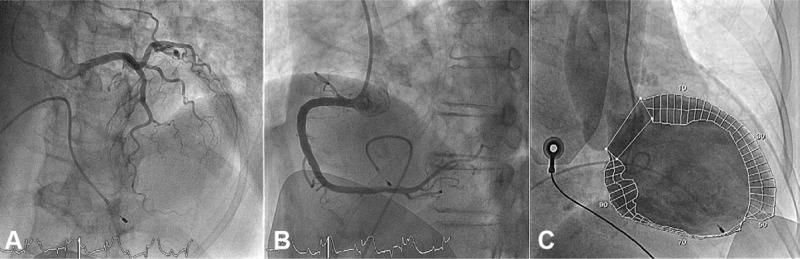

Both blood and urine cultures were positive for E coli. Regional inferior wall motion abnormalities on echocardiography, unexplained life-threatening arrhythmias, newly abnormal electrocardiogram, elevated cardiac troponins, and healthy coronary arteries on angiography were consistent with E coli-induced myocarditis.

The patient received implantation of a dual-chamber pacemaker because of irreversible CAVB.

血培养和尿培养均显示大肠杆菌阳性。超声心动图显示区域性下壁运动异常、不明原因的危及生命的心律失常、新出现的心电图异常、心肌肌钙蛋白升高以及血管造影显示冠状动脉正常,这些均符合大肠杆菌引起的心肌炎。

由于不可逆的CAVB,患者接受了双腔起搏器植入术。